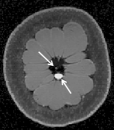

To examine the performance of our approach with brain MRI data when the assumptions of similarity between consecutive scans is not valid, we used retrospectively acquired data of a patient with GBM. The patient was scanned twice within an interval of five months, and exhibited changes between scans that occupy more than 50% of the brain region. We used T2-weighted FSE sequence (matrix: res = , 36 slices with thickness and no gap, TR/TE=, echo-train length=, flip angle=). We registered the follow-up scan to the baseline scan and examined the results of LACS-MRI (), CS-MRI and TCS-MRI with acceleration factors of 4, 6.4, and 10.6.

Table 3 shows the SNR values for different reconstructions and Figure 6 shows reconstruction results visually, at acceleration factor of 4 (25% of the k-space). In this case, there are major changes between the baseline and the follow-up scans due to therapy response. As a result, TCS-MRI exhibits poor performance in the vicinity of the changing tumor, since it is partially based on similarity between the consecutive scans, an assumption which is not valid in this case.

LACS-MRI, however, convergences to a result which is similar to CS-MRI. This is obtained thanks to the adaptive sampling and the weighting mechanism embedded in LACS-MRI, which reduces the weight given to the similarity to prior scan in the reconstruction process, if such a similarity does not exist.